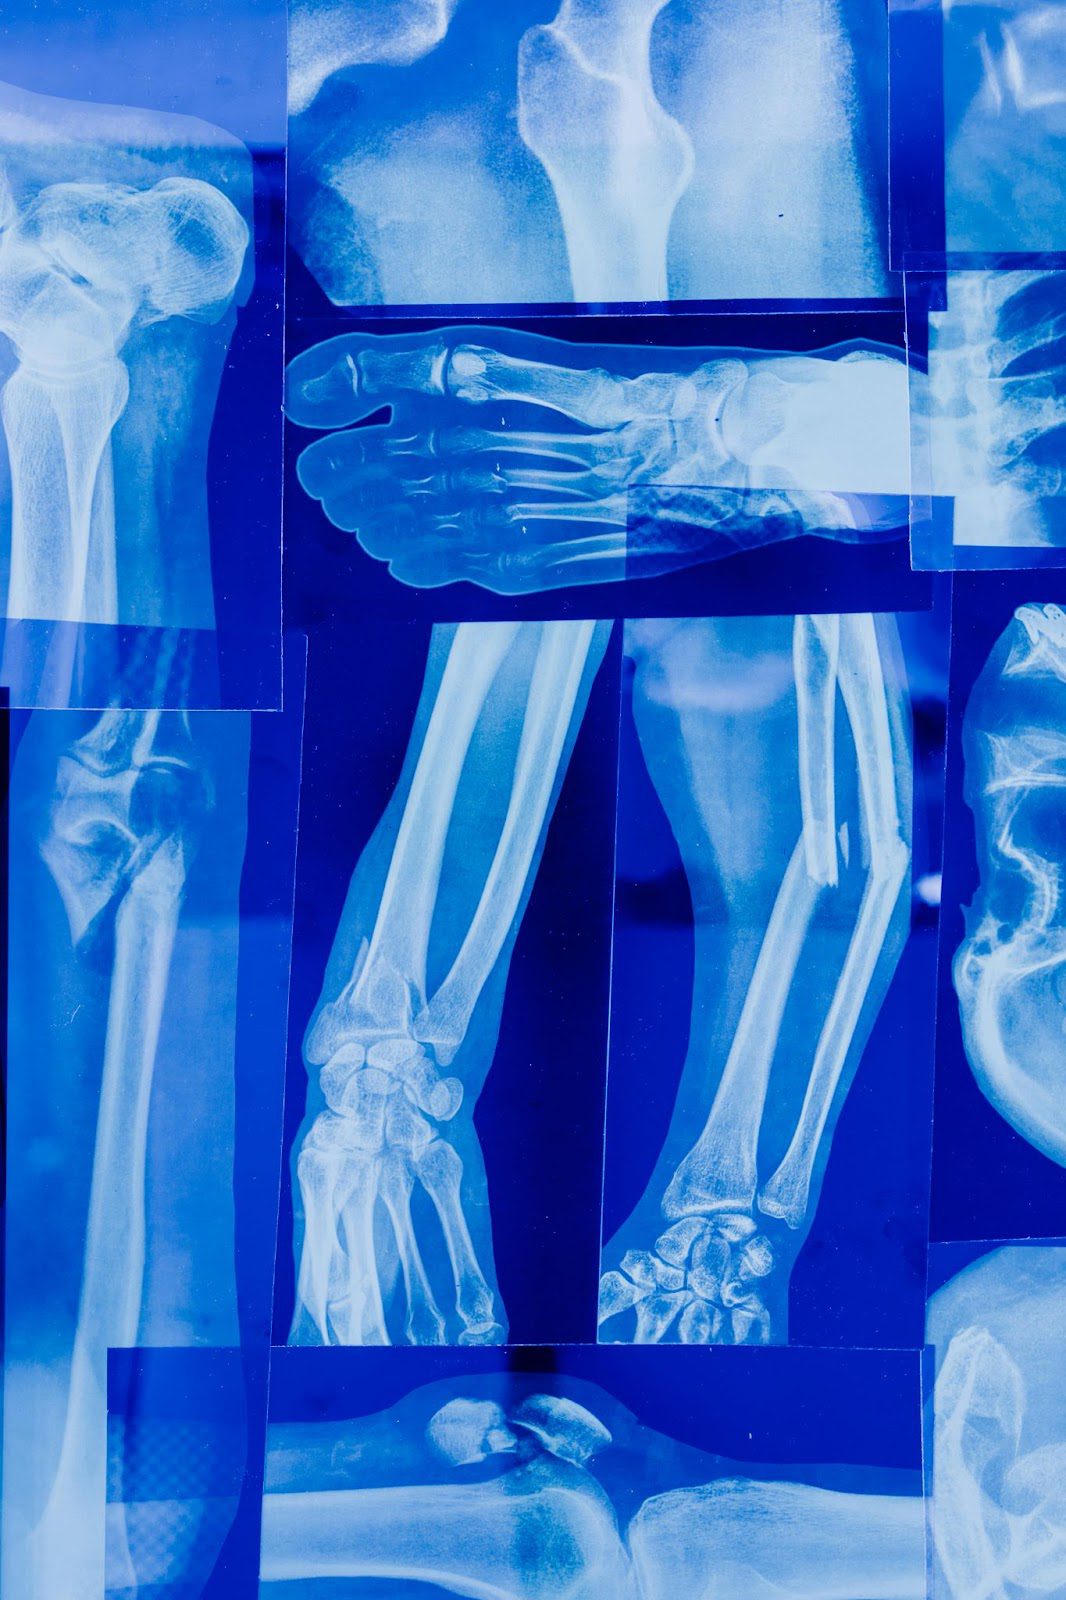

Not sure whether you’re dealing with a fracture vs sprain? While both injuries can cause pain and swelling, the treatment—and urgency—can be very different. Sprains may heal with rest, but fractures usually need medical care to prevent long-term issues. In this post, we’ll break down the key differences, symptoms to watch for, and how to properly diagnose and treat each type of injury.

What is a Fracture?

A ‘fracture’ is the medical term for a broken bone. It could be a partial or complete break. In some cases, a bone may be broken in multiple places.

Fracture vs Sprain: Do you have a broken bone?

If you can’t put weight on the injury, notice numbness or tingling, see a visible deformity, or heard a cracking sound at the time of impact, there’s a strong chance you’ve fractured a bone.